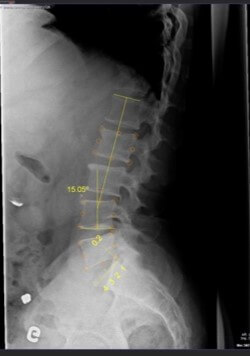

L’entreprise aspirait à intégrer dans son logiciel un outil capable de segmenter automatiquement les vertèbres sur des images à rayons X, facilitant ainsi le travail des chiropraticiens dans l’analyse et l’interprétation des clichés radiographiques.

Le CIMMI a conçu une librairie logicielle utilisant une technique de modèles déformables pour la segmentation précise des vertèbres. Cette solution innovante inclut un mécanisme d’alignement basé sur des modèles spécifiques à chaque vertèbre. L’utilisateur lance le processus en sélectionnant grossièrement une vertèbre sur l’image, après quoi l’algorithme affine la segmentation pour délimiter exactement le contour de la vertèbre ciblée.